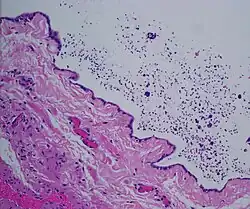

Spermatoceles can originate as diverticulum from the tubules found in the head of the epididymis. Sperm accumulation gradually causes the diverticulum to increase in size, causing a spermatocele. While there are many tubules connecting the epididymis to the testis, a blockage in one of the tubules may lead to formation of a cyst.[18] In many instances they appear to occur spontaneously without any preceding instances of injury.[6]

Scarring of any part of the epididymis due to trauma or inflammation can cause it to become obstructed and in turn form a spermatocele.[4]

The primary care physician may diagnose and manage benign causes of scrotal masses such as hydrocele, varicocele and spermatocele. However, if a "must not miss" diagnosis related to testicular masses such as testicular torsion, epididymitis, acute orchitis, strangulated hernia and testicular cancer is suspected, the family physician must refer to a urologist.[19] Finding a painless, cystic mass at the head of the epididymis that is clearly separate from the testicle can indicate a spermatocele. Shining a light through the mass, a process known as transillumination, can also help differentiate between a fluid-filled cyst and a tumor, which would not allow as much light to pass.[20] If uncertainty exists, ultrasonography of the scrotum can confirm the presence of a spermatocele.[7] The location and history of any scrotal masses are crucial in determining whether or not the mass is benign or malignant.[21] Lab tests such as a complete blood count (CBC test) or urine test can also be conducted to check for any possible infection or signs of inflammation.[22]